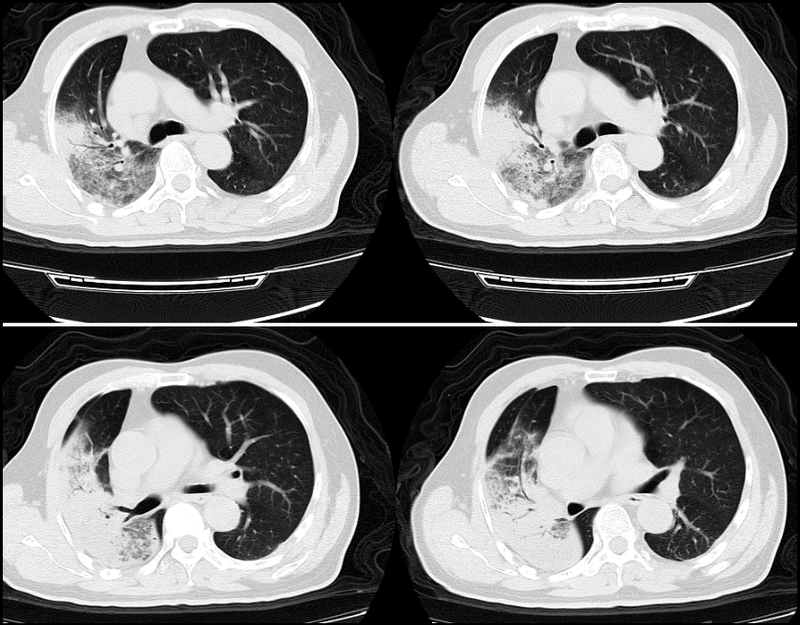

阳性支气管征和空气支气管征的异同:

阳性支气管征是直接通向肺内肿块或被包埋在肿块内的含气支气管影像。出现此征主要意味着较大支气管与肿块相通,和细支管征相比较只是支气管受累部位的不同,与枯树枝征也有差别,枯树枝征指的是一片肺组织病变内一个或多个受累的支气管气相改变,而阳性支气管征指的是肺内结节内的较大支气管受累的征象。就支气管形态改变而言,阳性支气管征针对肺内结节或肿块而言,枯树枝征是对一片受累的肺组织而言。

阳性支气管征主要反映支气管与肺内结节或肿块侵犯肺内支气管的表现,根据病变侵犯支气管位置的不同有以下表现:

1) 支气管到达肿瘤边缘被截断 ;

2)  支气管壁均匀或不均匀增厚,管腔规则或不规则狭窄;

3)  支气管深入肿瘤内部,肿瘤沿支气管管壁浸润;

4)  支气管壁受肿瘤挤压。

支气管肺癌起源于支气管,造成支气管形态的改变,所以肺内恶性结节尤其是腺癌出现此征的几率最大。而肺内的良性病变由于起源于肺间质或肺实质,对支气管的影响不大,所以此征相对少见。